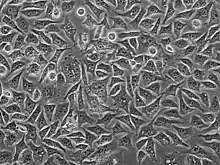

PC3 (PC-3) is a human prostate cancer cell line used in prostate cancer research and drug development. PC3 cells are useful in investigating biochemical changes in advanced prostate cancer cells and in assessing their response to chemotherapeutic agents. PC3 cells are also used to study viral infection in mammalian cells that exhibit an immune response[1]

PC3 cells have low testosterone-5-alpha reductase and acidic phosphatase activity, and do not express PSA (prostate-specific antigen). Furthermore, karyotypic analysis has shown that PC3 are near-triploid, having 62 chromosomes. Q-band analysis showed no Y chromosome. From a morphological point of view, electron microscopy revealed that PC3 cells show characteristics of a poorly-differentiated adenocarcinoma. They have features common to neoplastic cells of epithelial origins, such as numerous microvilli, junctional complexes, abnormal nuclei and nucleoli, abnormal mitochondria, annulate lamellae, and lipoidal bodies.